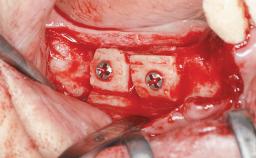

Shell Technique for Horizontal and Vertical Maxillary Bone Augmentation in a Partially Edentulous Patient with Aggressive Periodontal Disease

A 46-year-old woman was referred for treatment whose main complaints were mobility of her fixed partial dentures (right maxilla and left mandible) and periodontal bleeding during function. She also reported having taken systemic antibiotics to treat recurrent swelling in the area of the upper left molars. The patient had not seen a dentist for at least 2 years. She did not smoke and had no history of major systemic disease other than two minor orthopedic procedures some years back. The first-visit examination revealed poor plaque control, tooth mobility, periodontal disease, and a residual dentition widely associated with deep periodontal pockets.

Bone Augmentation Horizontal|Staged|Vertical

Augmentation Materials Autogenous chips|Autogenous block(s)|Xenogenous

Bone Volume Deficient vertically or deficient vertically AND horizontally